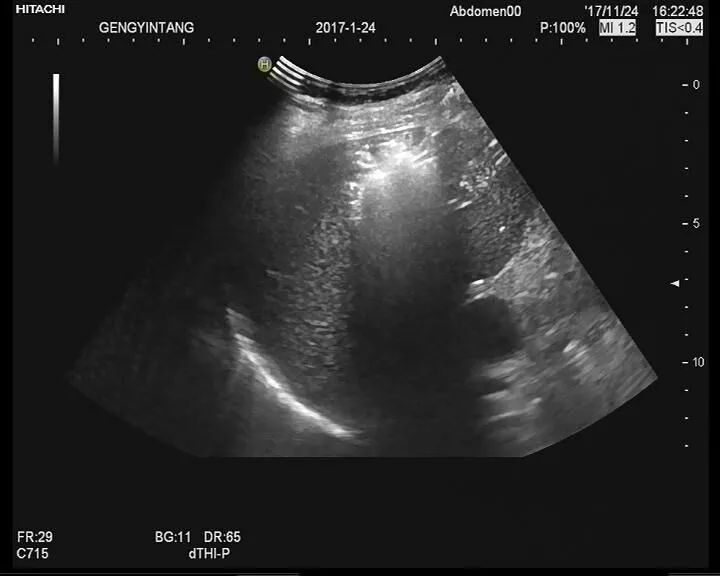

2、脓肿引流

用穿刺针经皮穿刺,并在 CT 扫描或超声内镜的引导下,对较大脓肿进行引流。如果排脓液有所帮助,患者可一直住院,直到症状已缓解,可以恢复软质饮食。如果引流不起作用,则需手术。